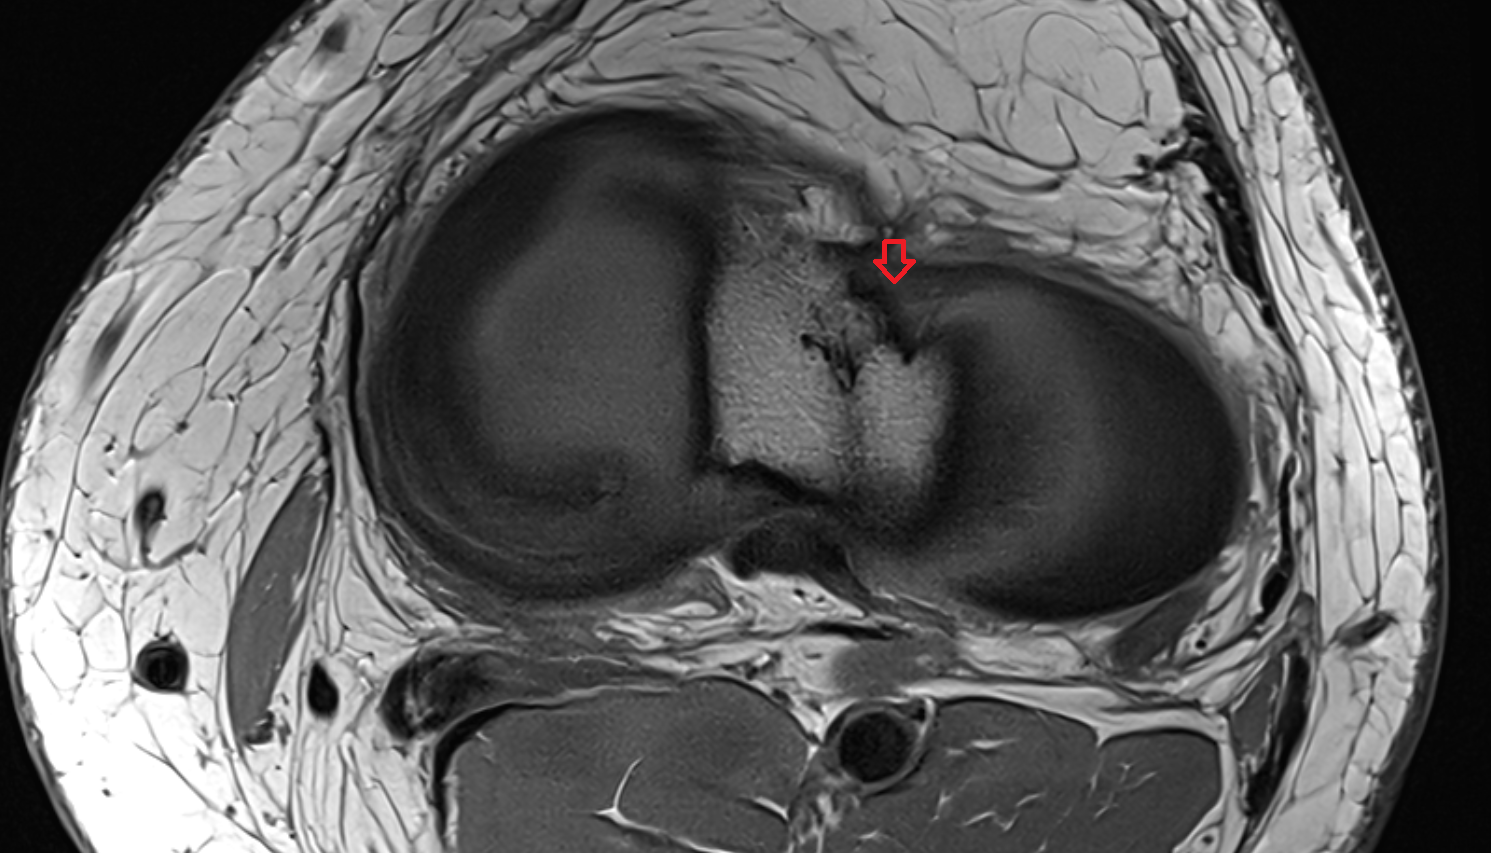

- Medial meniscus

- Lateral meniscus

- Anterior cruciate ligament

- Posterior cruciate ligament